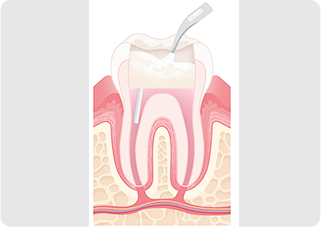

歯の内部、歯根部分の治療です

根管治療では、歯の根の中にある細い管状の空間(根管)から、感染した神経や細菌を丁寧に取り除き、専用の器具で内部を洗浄・消毒します。その後、すき間ができないよう薬剤で密閉し、再感染を防ぎます。根の状態によっては、治療を数回に分けて行うこともあります。

歯を抜かず、使い続けるために行います

強い痛みや歯ぐきの腫れ、歯根に膿が溜まるなどの症状があっても、適切な根管治療を行えば歯を残せる可能性があります。歯を支える根の中を清潔に保ち、再感染を防ぐことで、その歯を長く使い続けることができるのです。抜歯という最終手段を避けるための、大切な保存治療です。